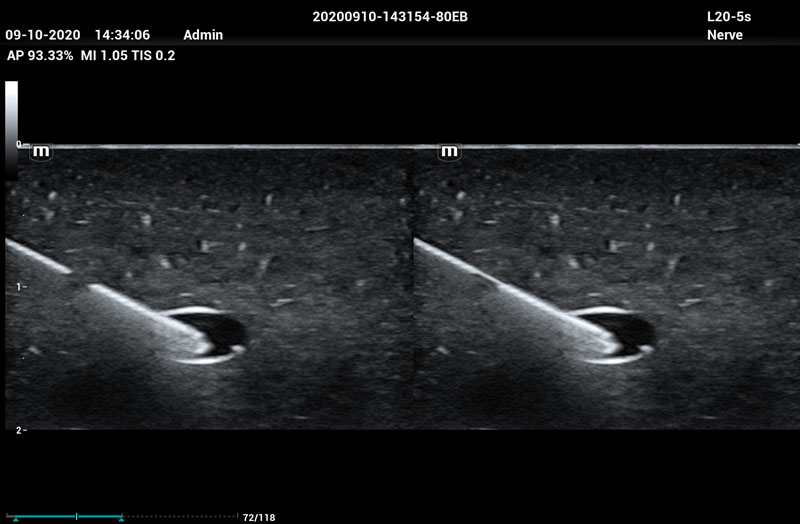

Needle Guidance